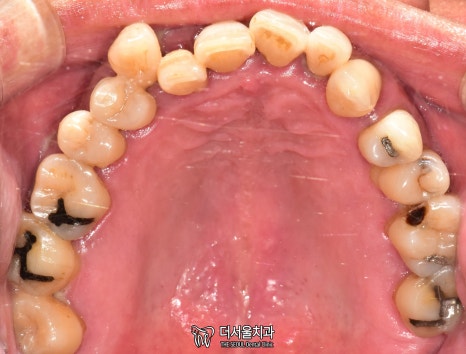

교합면을 확인했을 때도 마찬가집니다.

인접면에 있는 충치와

누워있는 사랑니까지 찾아볼 수 있었습니다.

단기간 내에 끝낼 수 없는 케이스죠.